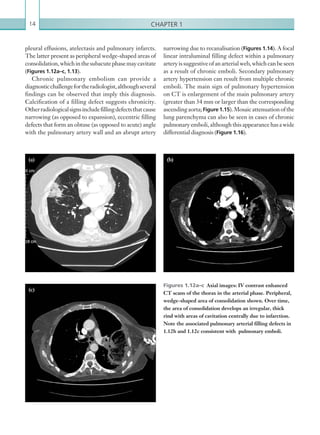

pleural effusions, atelectasis and pulmonary infarcts.

The latter present as peripheral wedge-shaped areas of

consolidation,which inthesubacutephasemaycavitate

(Figures 1.12a–c, 1.13).

Chronic pulmonary embolism can provide a

diagnosticchallengefortheradiologist,althoughseveral

findings can be observed that imply this diagnosis.

Calcification of a filling defect suggests chronicity.

Otherradiologicalsignsincludefillingdefectsthatcause

narrowing (as opposed to expansion), eccentric filling

defects that form an obtuse (as opposed to acute) angle

with the pulmonary artery wall and an abrupt artery

Figures 1.12a–c  Axial images: IV contrast enhanced

CT scans of the thorax in the arterial phase. Peripheral,

wedge-shaped area of consolidation shown. Over time,

the area of consolidation develops an irregular, thick

rind with areas of cavitation centrally due to infarction.

Note the associated pulmonary arterial filling defects in

1.12b and 1.12c consistent with pulmonary emboli.